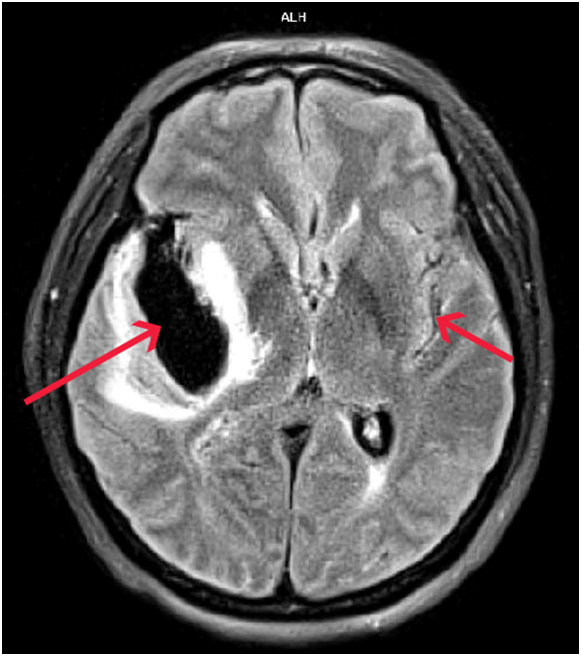

當腦動脈瘤滲漏或破裂,血液會溢出大腦表面(蜘蛛膜下腔),患者會感到爆裂性頭痛;其他症狀包括噁心和嘔吐、頸部僵硬、畏光、精神錯亂、虛弱和喪失意識。嚴重SAH更會導致血管痙攣令大腦供氧減少,或血液在大腦周圍積聚而造成腦積水。

腦動脈瘤一旦出現滲漏或破裂須進行緊急手術,要盡快通過手術夾閉或堵塞腦動脈瘤以防止再出血或擴大(請參閱以下圖表)。如腦內血塊壓迫腦部影響供血,應即時進行手術移除血塊,並考慮放置支架引流腦積水及減低腦壓。然而,考慮到某些特殊情況,例如病人處於昏迷狀態、本身有嚴重疾病、高齡等,一般要等到病情穩定才安排治療。

(特此致謝聖德肋撒醫院掃描部提供醫學影像圖片)